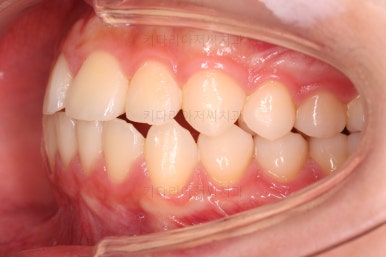

초진 시 다른 부위들 사진입니다.

약간의 주걱턱 느낌에 약간의 돌출감, 전반적인 치열의 가지런한 느낌은 나쁘지 않았지만 약간의 불량한 교합상태였어요.

다른 부분은 크게 바꾸지 말고 약간의 교합조절과 어금니 치료에 초점을 맞춰서 교정치료 계획을 잡았습니다.